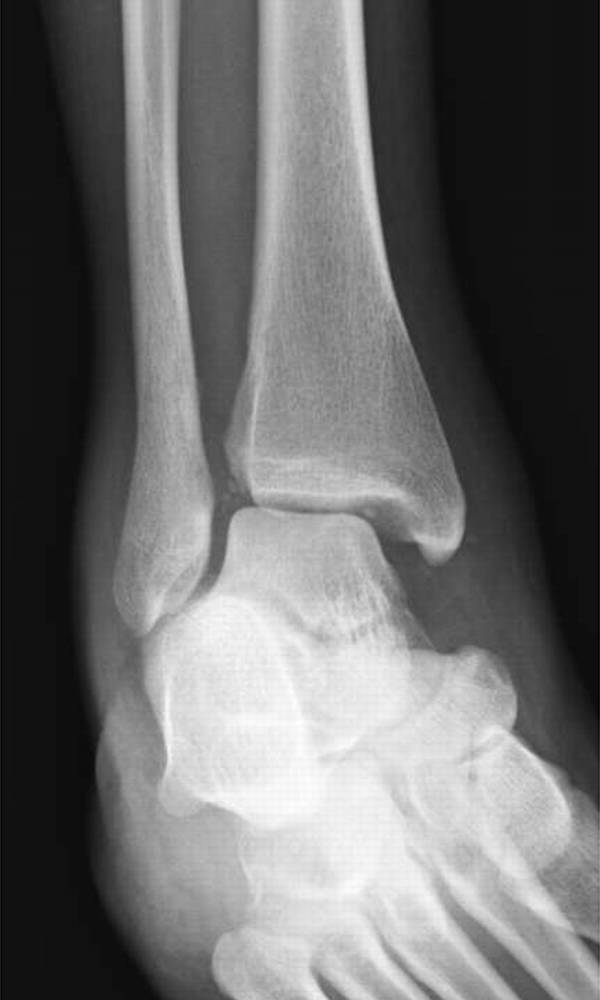

在脚踝处,必须警惕超出投照视野(图4)的足部腓骨骨折的可能性和足部骨折的可能性。例如,Maisonneuve骨折是一种旋前 - 旋转损伤,伴有远端胫腓骨间继位断裂和近端腓骨骨折[19]。了解骨折模式与相关的损伤机制模式至关重要,特别是在踝关节[20]。

图。4A-28岁女子在地面跌倒后。A,踝关节的斜视图显示继发性加宽和微小的内侧踝撕裂性骨折。B,近侧腿的侧视图显示倾斜的近端腓骨骨折,构成Maisonneuve骨折。